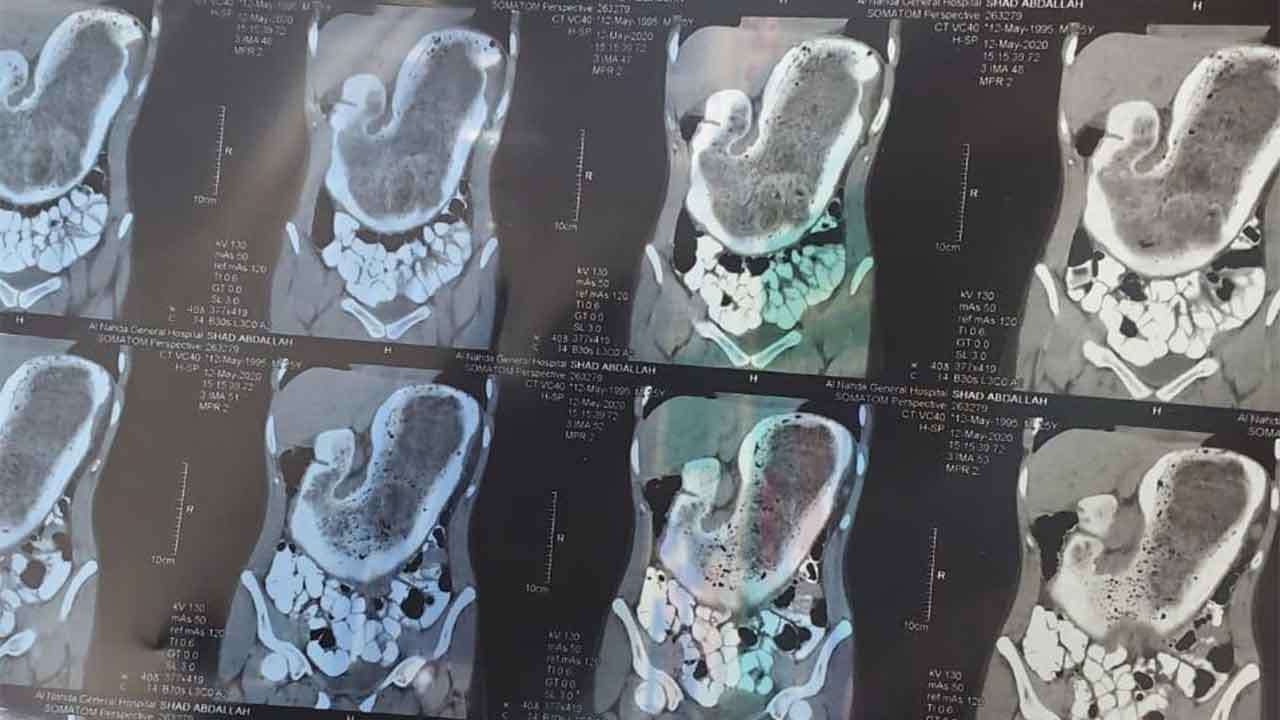

صورة أشعة للمريضة. صحيفة "عاجل"

أخرج فريق طبي بالطائف، 2 كيلو من الشَعر داخل بطن فتاة عشرينية، في الطائف، بالمملكة العربية السعودية، بعدما لازمتها آلام مزمنة. بحسب صحيفة " عاجل" الإلكترونية

الفتاة عانت أوجاع متكررة مستمرة، لكن تحول الألم إلى شيء لايطاق قادها إلى طوارئ مستشفى الملك عبدالعزيز التخصصي بالطائف، بعد أن أعياها الألم ووصلت معه إلى حد لا تستطيع مقاومته، لتخضع لفحص سريري موسع، انتهى بالوصول لعلة الفتاه منذ سنوات، بعد اكتشاف جسم غريب يتمحور داخل البطن ويشكل جدارًا خانقًا للمعدة.

وعلى الفور قرر الفريق الطبي، إجراء تدخل جراحي عاجل للوصول للجسم الغريب ليكتشفوا لاحقاً أن ما كان يحيط بالمعدة وكان سبب آلام سنوات مضت، عبارة عن تشكل مترابط من الشعر يزن 2 كيلو جرام، استطاعا التكتل حول جدار المعدة داخل تجويف البطن مع تزايد نموه في حالة طبية نادرة الحدوث، وتم استخراج الكتلة وإنهاء معاناة الفتاة.